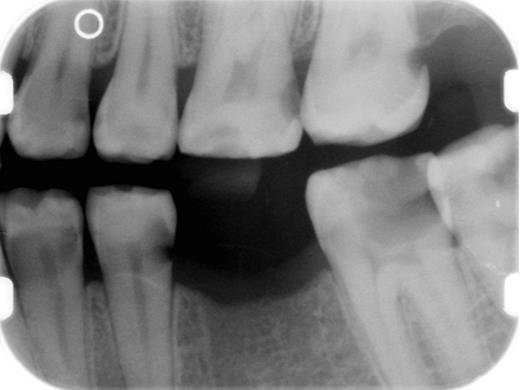

Prevention of dental caries is a critical component of salivary gland cGVHD management, and we initiate these measures in all patients with clinically significant disease (Table 4). Patients should be continuously reminded of the importance of maintaining a noncariogenic diet and good oral hygiene. In patients with severe salivary gland hypofunction, even when tooth brushing after eating is not feasible, patients should be instructed to rinse their mouths well with water. Prescription 1.1% sodium fluoride gel should be applied to the teeth nightly, either using a toothbrush to “paint on” to the teeth, or via custom-fitting trays that can be fabricated by the patient's dentist.68,69 In addition to topical fluoride, emerging evidence supports the use of a calcium/phosphate-based remineralizing agent (eg, GC MI Paste Plus, GC America), which can be applied just before topical fluoride.70,71 Dentists can place fluoride varnish twice annually during recall visits for further protection. Bitewing radiographs should be obtained on an annual basis to screen for interproximal decay (Figure 15), and areas of decay should be treated promptly and definitively (ie, the full extent of caries must be removed as risk for recurrent decay is high).

Intaoral bitewing radiograph demonstrating multiple interproximal dental caries (radiolucencies) in a patient with salivary gland chronic GVHD.